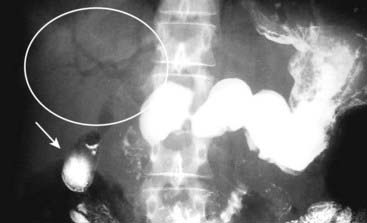

Figure 15-12 Pneumatosis seen en face.

Close-up of the right lower quadrant in another infant shows multiple faint, mottled lucencies in the right lower quadrant (white circle), which is the appearance of pneumatosis intestinalis when seen en face. The density has the same appearance as air mixed with stool, but can be distinguished from stool because it occurs in areas stool might not be expected and it does not change over time. This infant also had necrotizing enterocolitis.